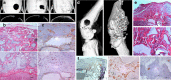

Clinical interest on human mesenchymal progenitor cells (hMPC) relies on their potential applicability in cell-based therapies. An in vitro characterization is usually performed in order to define MPC potency. However, in vitro predictions not always correlate with in vivo results and thus there is no consensus in how to really assess cell potency. Our goal was to provide an in vivo testing method to define cell behavior before therapeutic usage, especially for bone tissue engineering applications. In this context, we wondered whether bone marrow stromal cells (hBMSC) would proceed in an osteogenic microenvironment. Based on previous approaches, we developed a fibrin/ceramic/BMP-2/hBMSCs compound. We implanted the compound during only 2 weeks in NOD-SCID mice, either orthotopically to assess its osteoinductive property or subcutaneously to analyze its adequacy as a cell potency testing method. Using fluorescent cell labeling and immunohistochemistry techniques, we could ascertain cell differentiation to bone, bone marrow, cartilage, adipocyte and fibrous tissue. We observed differences in cell potential among different batches of hBMSCs, which did not strictly correlate with in vitro analyses. Our data indicate that the method we have developed is reliable, rapid and reproducible to define cell potency, and may be useful for testing cells destined to bone tissue engineering purposes. Additionally, results obtained with hMPCs from other sources indicate that our method is suitable for testing any potentially implantable mesenchymal cell. Finally, we propose that this model could successfully be employed for bone marrow niche and bone tumor studies.